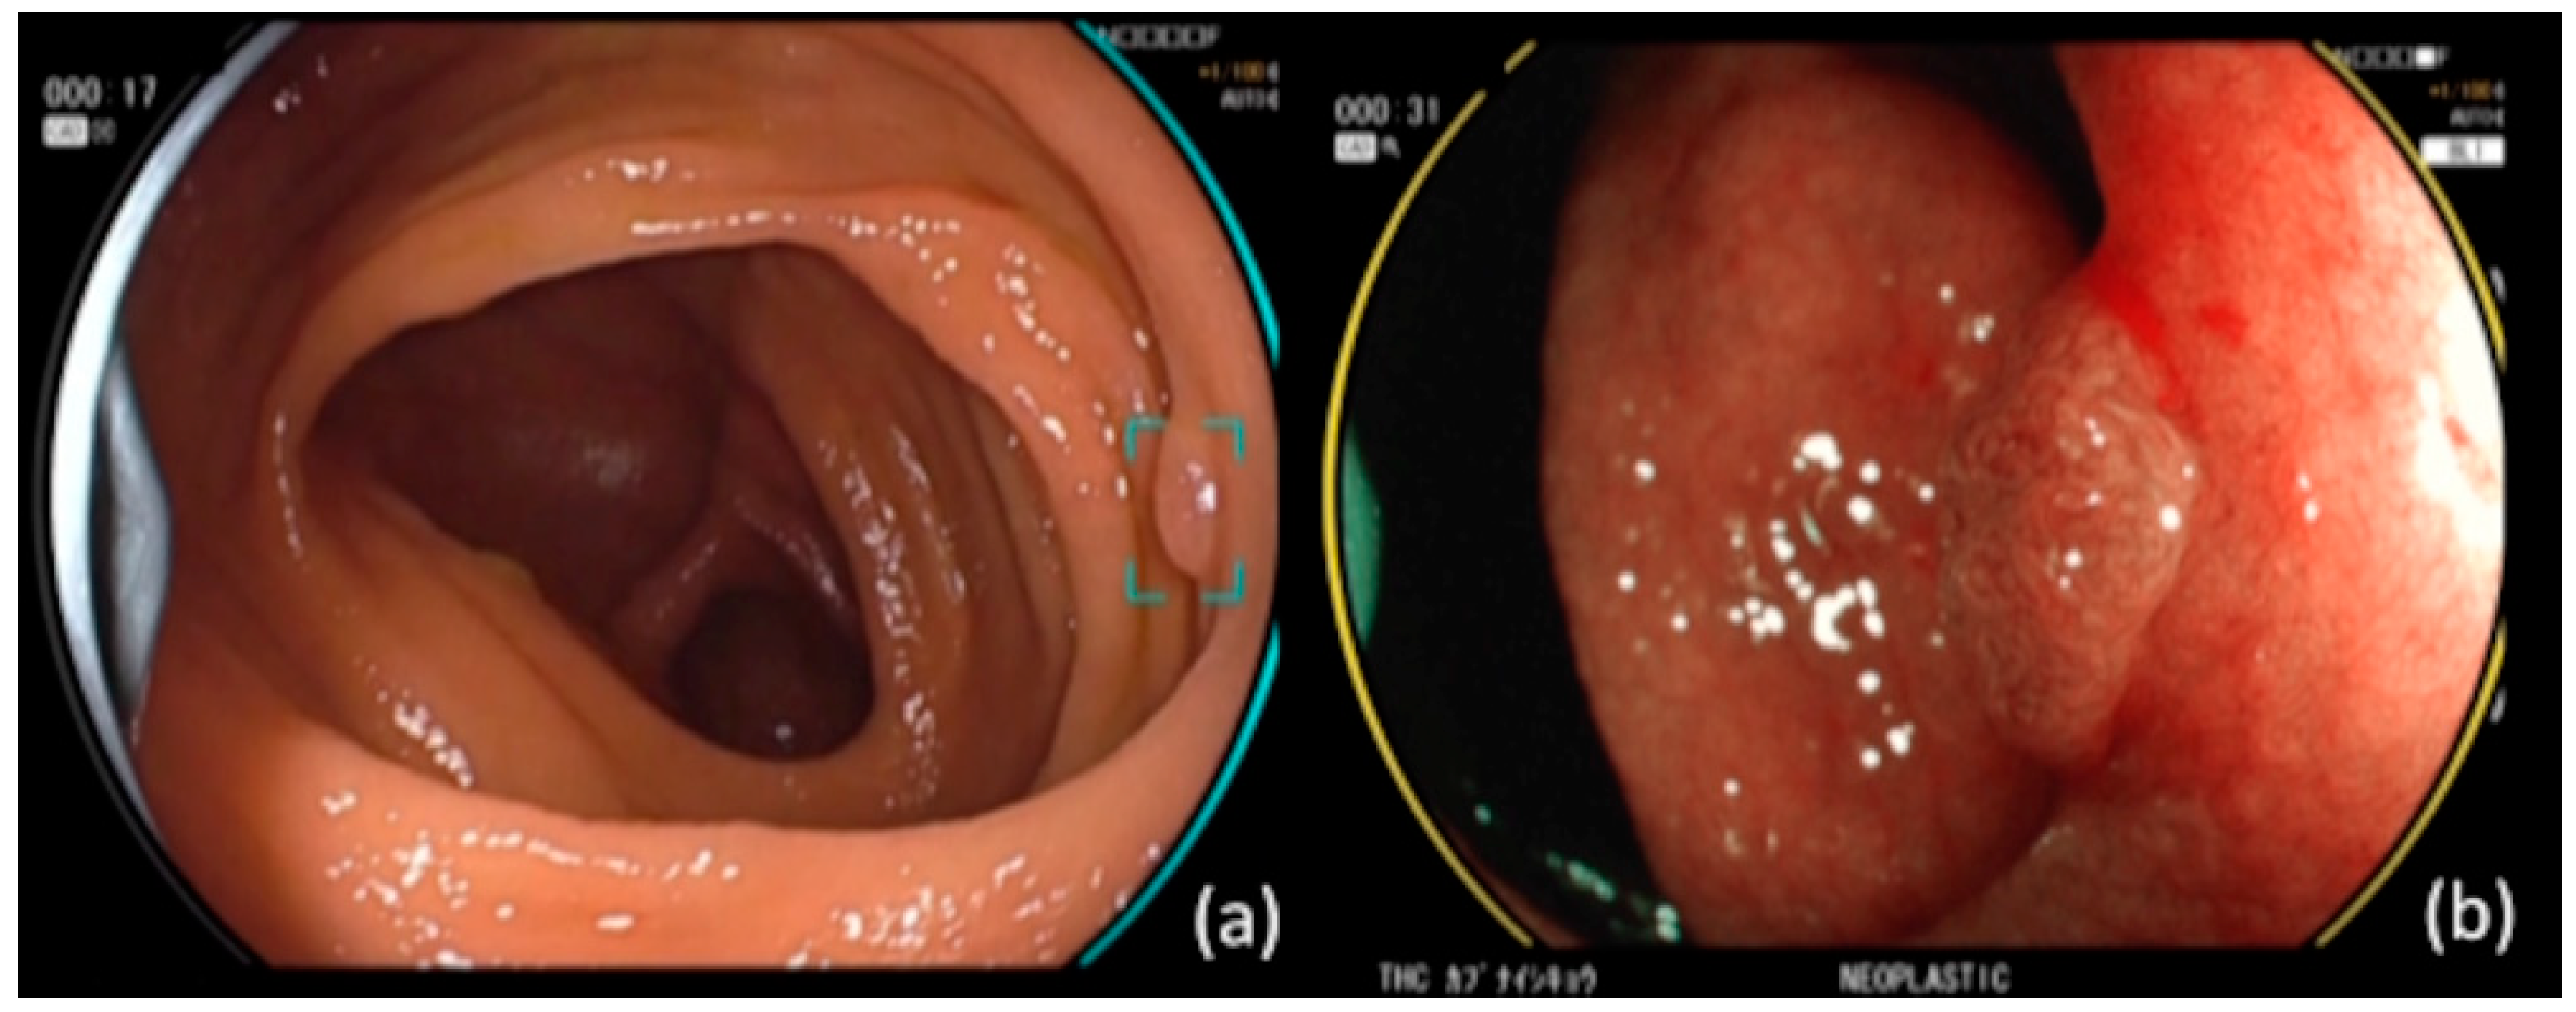

Figure 1.

(a) CAD EYE endoscope with CADe function. The device detects lesions and displays targets. In this case, the target remained visible because there was a lesion. (b) CAD EYE endoscope with CADx function. Switching to BLI shows a qualitative diagnosis of the lesion. Since the lesion was neoplastic, it displayed a yellow circular flame.